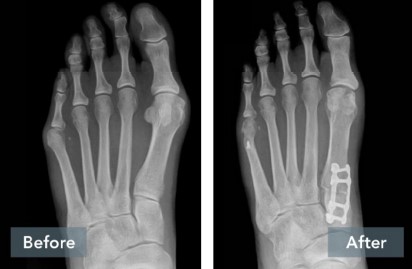

A common misconception is that a bunion is simply a “bump” that can be “shaved off.” But, bunions are more than a bump – they are complex 3D problems caused by an unstable joint in the middle of the foot. While the majority of bunion surgery is only 2D and fails to address the root cause, the Lapiplasty® Procedure provides a 3D correction and secures the unstable joint.

While traditional 2D osteotomy surgery cuts & shifts the bone to address the cosmetic bump, Lapiplasty® 3D Bunion Correction® does more – it corrects the entire bone in 3D and secures the unstable foundation to get you back on your feet typically within 3-1 0 days in a walking boot. The Lapiplasty® Procedure has also shown low recurrence; 97% and 99% maintain 3D correction in 13 and 17 months respectively.